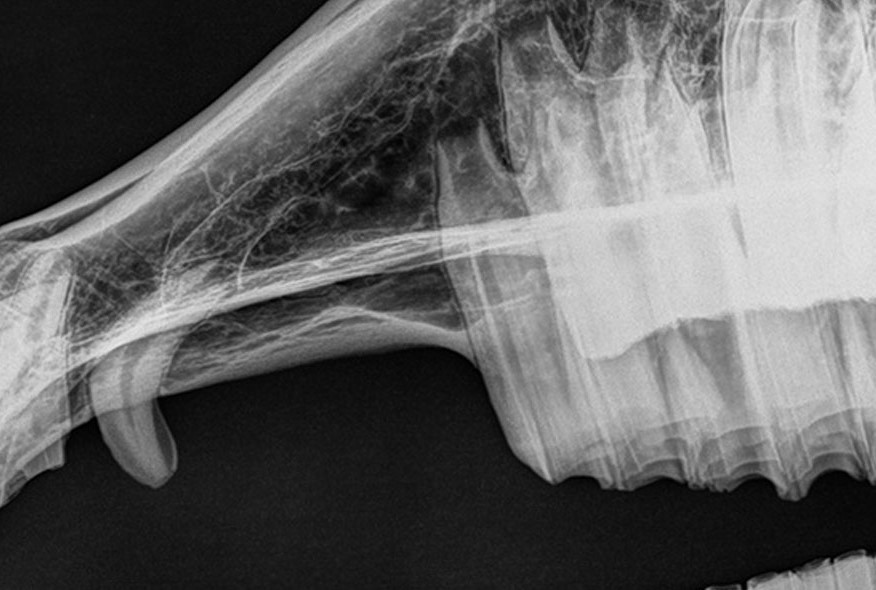

Adobe Veterinary Center offers advanced equine radiology using digital x-rays for fast, accurate diagnosis of lameness, fractures, and other conditions, ensuring precise treatment and minimal radiation exposure.

Digital x-rays are great for diagnosing lameness in horses. We can quickly and efficiently diagnose your horse, whether he or she is suffering from laminitis, a broken bone, or anything else.